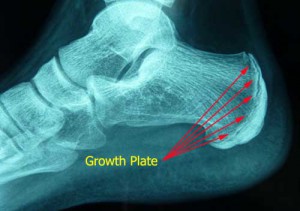

Heel pain can also occur in children although the mechanism behind this pain is generally different, it is often a result of growth. Activity inflames the growth plate in the heel, it is most common between the ages of 8 and 13 and we often find these children exhibit an excessive amount of pronation. At Brighton Podiatry we deal with this problem quite frequently and we aim to keep your child as active as possible. Just because a child has heel pain does not mean they cannot play sport. If your child has heel pain give us a call and make an appointment.